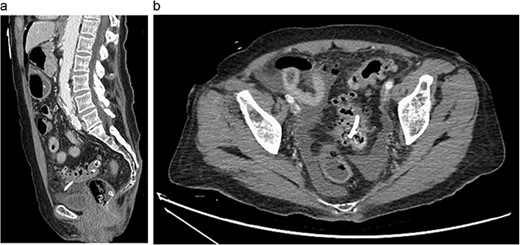

A 79-year-old female presented to the emergency department with progressively worsening abdominal pain, nausea, vomiting, intermittent chills, and non-bloody mucoid bowel movements. Her medical history was significant for a previous cardiovascular accident, dementia, emphysema, hypertension, gastroesophageal reflux disease, diverticulosis, type 2 diabetes mellitus, and hypothyroidism. The patient’s surgical history included a recent endoscopic retrograde cholangiopancreatography with biliary sphincterotomy, debris removal, and stent placement for acute cholangitis with choledocholithiasis. At that time, an 8.5 Fr × 7 cm straight plastic biliary stent was inserted in the common bile duct followed by a robotic-assisted laparoscopic cholecystectomy during the same admission. Two weeks later, an outpatient esophagogastroduodenoscopy (EGD) was performed for the removal of the biliary stent; however, it was not visualized protruding from the major duodenal papilla. Abdominal and pelvic radiographs revealed the migrated stent overlying the pelvis within the region of the sigmoid colon (Fig. 1). Given her stable clinical presentation, gastroenterology decided to wait for the stent to spontaneously pass.

Eleven days later, the patient presented to the emergency department with abdominal pain. During transit to the hospital, she exhibited mild hypotension with a systolic blood pressure in the 90s and was given 500 cc of intravenous normal saline. Upon arrival, her vital signs had stabilized with a temperature of 36.4°C, blood pressure of 122/63 mmHg, heart rate of 81 bpm and oxygen saturation of 94% on room air. Physical examination revealed a moderately distended, rigid abdomen with diffuse tenderness and involuntary guarding. Biochemical investigations demonstrated a leukocyte count of 4.2 x 109 K/µL and a lactate of 3.2 mmol/L. Liver function tests, coagulation profile and electrolytes were unremarkable. Computed tomography (CT) imaging of the abdomen and pelvis with intravenous contrast demonstrated free fluid in the peritoneal cavity with moderate scattered pneumoperitoneum and migrated biliary stent that extended from the sigmoid colon into the peritoneal cavity (Fig. 2).

Abdominal CT showing migrated biliary stent that perforates the sigmoid colon in the sagittal (a) and axial (b) views. Pneumoperitoneum and free fluid in the pelvis are also noted.